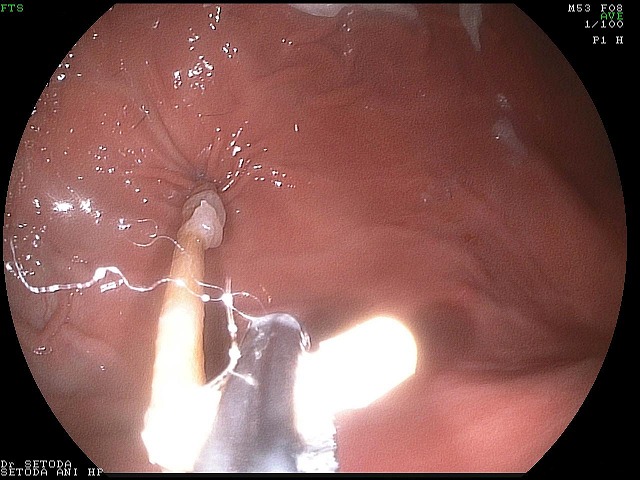

つまようじが胃から十二指腸の中に入り始めている状態でした。

いったん引きだして、胃の中でつまようじの状態を調べてみると一部折れ曲がっています。

胃の中からつまようじを取り出す際に、胃や食道に傷をつけないように取り出すために、この折れ曲がった部分を持って、取り出すことにしました。